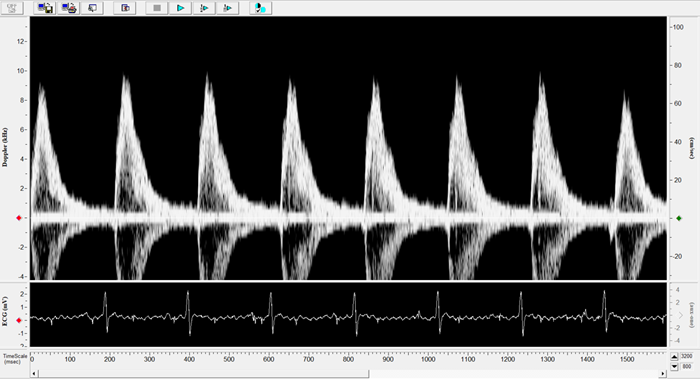

Imaging gallery - Doppler Flow Velocity System

Mouse - Abdominal Aorta. Image Credit: Scintica Instrumentation Inc.